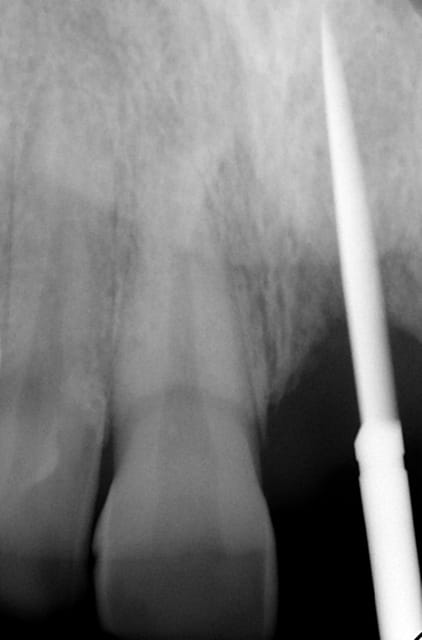

J'ai de tout en boutique..jeune homme 25 ans accident de piscine choc sur la bordure ( fêlure existante..fistule), extraction le jour même, temporisation 4 mois (avec un bout de trombone) Monobloc 16mm 60N, prep cap zircone droit 2/2 provisoire ion, temporisation 3 mois ceramo ceram..

Au contraire..si tu regarde attentivement les radios tu veras qu'en quelques mois il y a une néoformation osseuse autour des micros spires. On voit un manque le jour de la pose et plus d'os avec la Procera. Volontairement j'ai pas plus enfoncé l'implant ..Si j'avais ouvert j'aurai bousillé tout le potentiel cicatriciel..Charon l'a démontré depuis longtemps en paro. Aux patient je leur explique que "Ouvrir c'est comme tondre le gazon avec un motoculteur" .

Donc il y maintien et renfort du parodonte.